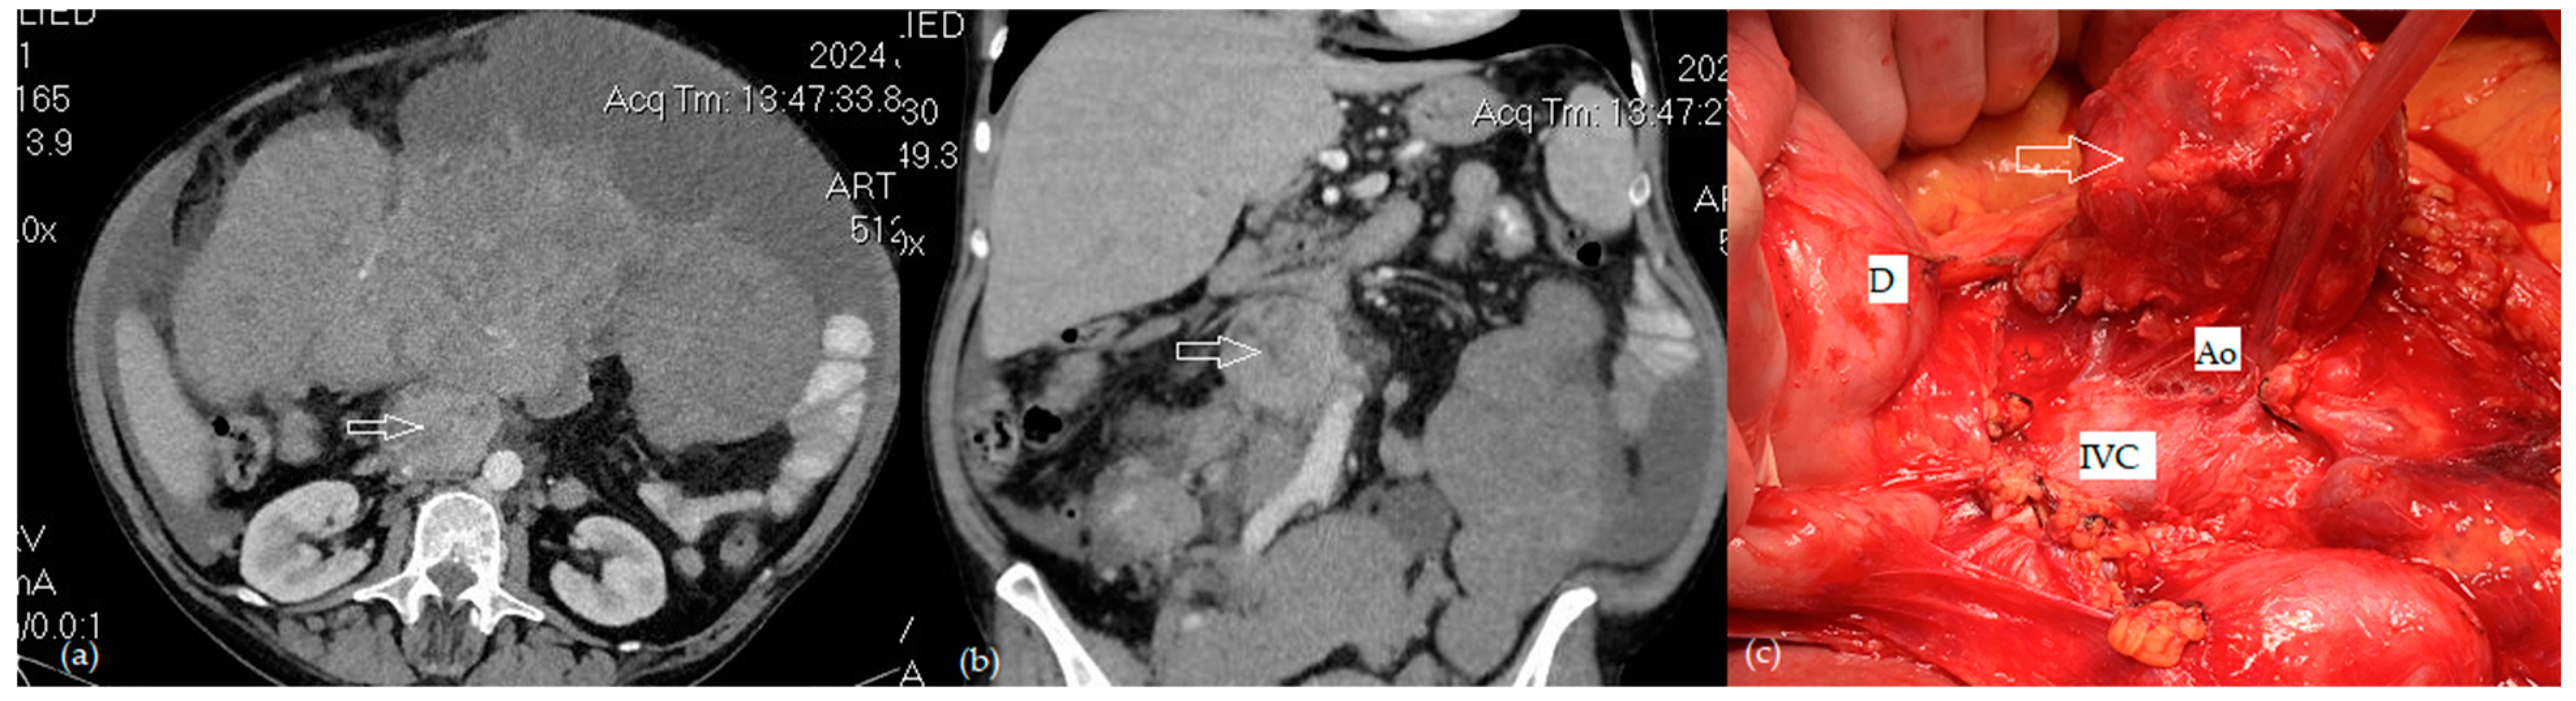

- Benoit, L.; Zerbib, J.; Koual, M.; Nguyen-Xuan, H.; Delanoy, N.; Le Frère-Belda, M.-A.; Bentivegna, E.; Bats, A.-S.; Fournier, L.; Azaïs, H. What Can We Learn from the 10 Mm Lymph Node Size Cut-off on the CT in Advanced Ovarian Cancer at the Time of Interval Debulking Surgery? Gynecol. Oncol. 2021, 162, 667–673. [Google Scholar] [CrossRef] [PubMed]

- Tardieu, A.; Ouldamer, L.; Margueritte, F.; Rossard, L.; Lacorre, A.; Bourdel, N.; Lades, G.; Sallée, C.; Monteil, J.; Gauthier, T. Assessment of Lymph Node Involvement with PET-CT in Advanced Epithelial Ovarian Cancer. A FRANCOGYN Group Study. J. Clin. Med. 2021, 10, 602. [Google Scholar] [CrossRef] [PubMed]

- Crestani, A.; Huchon, C.; Mezzadri, M.; Marchand, E.; Place, V.; Cornelis, F.; Touboul, C.; Haddad, B.; Dabi, Y.; Benifla, J.-L.; et al. A Pre-Operative Radiological Score to Predict Lymph Node Metastasis in Advanced Epithelial Ovarian Cancer. J. Gynecol. Obstet. Hum. Reprod. 2022, 51, 102464. [Google Scholar] [CrossRef] [PubMed]